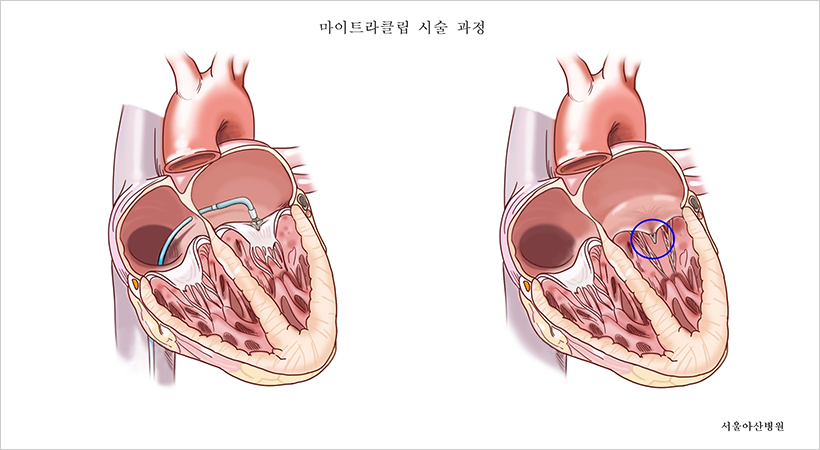

마이트라클립은 승모판막을 구성하는 두 개의 판 사이를 클립처럼 집어서 판막이 열리고 닫힐 때마다 생기는 빈틈을 없애 혈액 역류를 감소시키는 기구다. 개흉 수술 없이 사타구니 정맥을 통해 가느다란 관을 넣어 심장 내부에 도달한 후 승모판에 클립을 장착한다.

서울아산병원 심장병원 통합진료팀은 고위험군의 환자인 김 씨가 보다 안전하게 치료받을 수 있도록 개흉수술 없이 마이트라클립 2개를 승모판에 시술함으로써 승모판 역류증을 치료했으며, 회복기간도 짧아 김 씨는 시술 5일 후 퇴원했다.